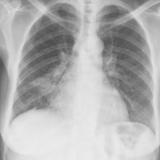

Lobar Collapse

LUL Collapse

Album: LUL Collapse